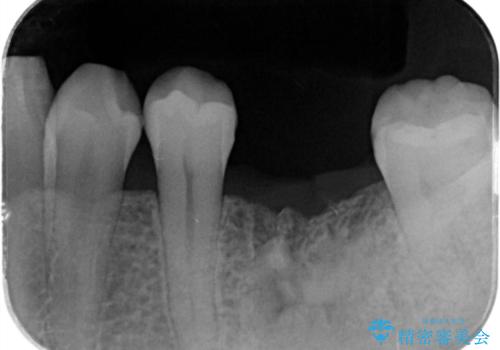

- 左下大臼歯が噛みしめにより割れてしまい、抜去後のインプラント治療を希望され来院されました。

しっかりと咬合負担能力の増えるインプラントによる欠損補綴を計画します。